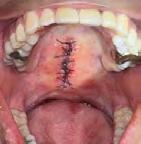

periodontal, colocándolo en solu ción fisiológica al 0.9%, mientras se continúa con la extracción dental del primer molar inferior izquierdo y mínima manipulación del alveolo (Figura 3), para posterior trasplante del tercer molar y finalizando afron tando el lecho quirúrgico con un pun to en forma de cruz con sutura sobre el diente trasplantado y radiografía de control posoperatorio (Figura 4 y 5). Se prescribieron antibióticos de la familia de los betalactámicos y analgésicos para complementar su

Figura 3. Alveolos dental postextracción de primero y tercer molar inferior izquierdo. Figura 4. Punto de sutura en cruz para estabilidad de tercer molar inferior izquierdo y cierre del resto de las heridas. Figura 5. Radiografía dentoalveolar postoperatoria.